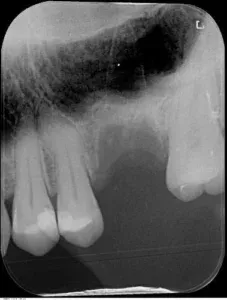

La perdita dei molari superiori lascia in nella maggior parte dei casi una quantità ossea molto ridotta per l’estensione dei seni paranasali (cavità appartenenti al sistema aereo nasale, atte al riscaldamento dell’aria inalata), tale da non permettere l’inserimento impiantare nel modo classico.

–il grande rialzo di seno: permette, in casi in cui l’osso residuo è estremamente ridotto, di ottenere grazie all’inserimento di una maggior quantità di osso sintetico la neoformazione di osso naturale in tempi che variano dagli 8 ai 12 mesi.

La scelta deve comunque essere effettuata in base al caso clinico, dopo aver effettuato gli esami radiografici necessari (OPT e/o TAC) e alle condizioni di salute del paziente.